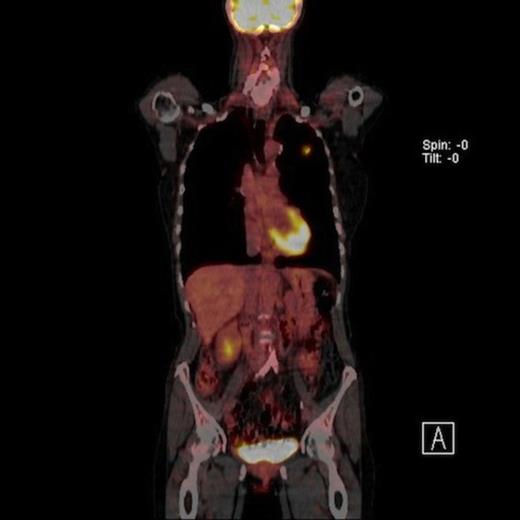

A 61-year-old female smoker (42 pack years) was found to have left upper zone shadowing on chest X ray following a history of weight loss. Her performance status was 1 with a Forced expiratory volume in one second (FEV1) of 1.94 Litres. Positron emission tomography in conjunction with computed tomography (PET-CT) showed two nodules in the left upper lobe. There was a 2cm spiculated lesion in the anterior segment with a Standardised Uptake Value (SUV) max of 5.6 units (Fig 1A) and a 2.2 cm cavitating lesion in the apico-posterior segment with a SUV max of 2.7 units (Fig 1B). There was no radiologic evidence of mediastinal lymhadenopathy or distant metastases.

Coronal view PET CT scan of a high uptake nodule in the left upper lobe